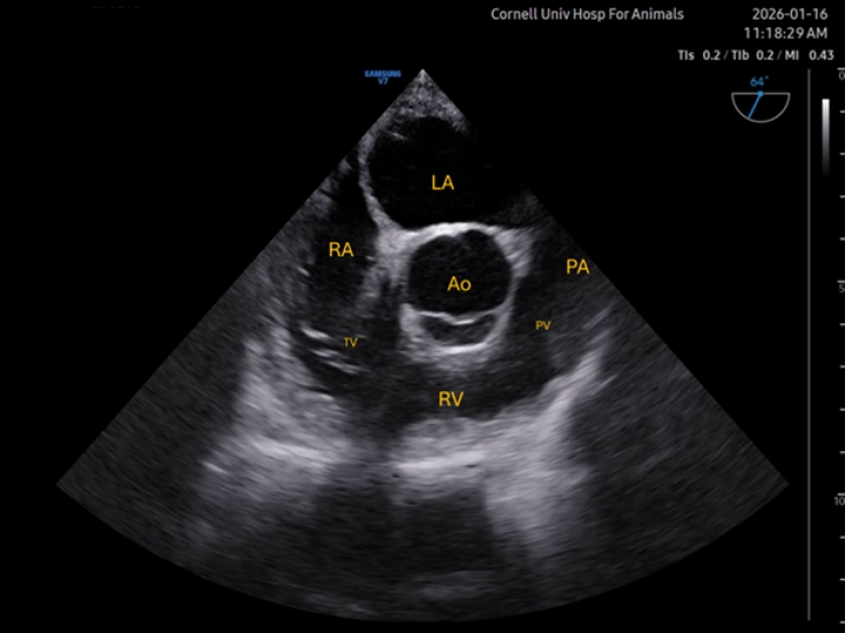

Mid-esophageal right ventricular inflow-outflow (ME RV I-O)

Also starting from a short axis view of the aortic valve, rotation of the omniplane to 60-80° is applied. The probe itself might need to be rotated too in order to bring the tricuspid valve, right ventricle, and pulmonary valve (PV) into view. The pulmonary artery (PA) can be observed too. The aortic valve is typically seen at the center of the image. Reflux through the tricuspid valve can often be assessed on this view, as well as dilation of the right ventricle, often secondary to increases in the afterload. Passage of pulmonary artery catheters can also be guided with this view.